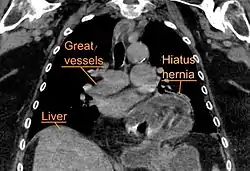

A hiatal hernia as seen on CT

A large hiatal hernia as seen on CT imaging